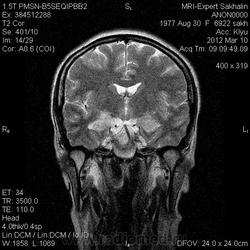

Направительный диагноз:головная боль напряжения.

Краткий анамнез заболевания, жалобы: головные боли,снижение памяти, раздражительность, снижение аппетита в течение 3-х месяцев.

Подозреваю демиелинизацию,гиппокампальный склерз ( тогда базальные ядра и ножки при чем?),ишемические проявления -не знаю!Помогите , пожалуйста, начинающему доктору!

Лимбический энцефалит? Паранеопластический процесс? А где диффузионные программы- не помешают. Нужно подумать (или спросить у ннемо, например))).

Написала дифф.ряд: лимбический энцефалит, лимфому ЦНС, герпетический энцефалит.

С лимфомой верифицированной не встречался, картина не противоречит паранеопластическому или герпетическому энцефалиту. Склероз гиппокампов: нет уменьшения их размеров, зоны изменений сигналов гиппокампами не ограничиваются, есть кроме височных долей и в ножках мозга, опять же накопление контраста.

Женщина 1977 года рождения.Со слов мужа , около 3/х мес. назад начались головные боли, снижение памяти, раздражительность снижение аппетита.Перенесла какую-то инфекцию типа ОРЗ.С ней разговаривать трудно-мало что помнит.На асоциальную , наркоманку не похожа-приличная с виду женщина.Неврологический статус хотела выяснить у лечащего врача по телефону, но она живет в районе,и телефон не указала .Визуально-неврологический статус без особенностей.В направлении-головная боль напряжения .Нет указаний -на что обратить внимание.

Ишемические изменения и темпоральный склероз - нет.

Для И.Бондаренко - вы все правильно указали - гипер- в Т2W, а также гипо- в Т1W, + очаги накопления контраста

Есть и давно подтвержденное понятие паранеопластический лимбический энцефалит - как вариант примерно так и будет выглядеть.

В данном случае больше данных за воспалительный энцефалит - есть синусит (не нравиться гиперинтенсивное включение парацентрально в пазухе -грибок????) .

С учетом накопления контраста да и по локализации однозначно не опухоль, не инсульт, не травма. Из классики да действительно герпес любит виски, также и иные вирусные могут быть (этиологию иной раз не угадаешь - бессмыслено), может быть и тбс. но сос четов не сбрасывал бы паранеопластический - тем более женщина да и контраст накопила как бы не молочка?? Ну и совсем чтоб запутать нет ли В20? только на внешний вид и на мужа не надо ориентироваться - у нас и у врачей и у студентов мед вузов бывает - пройденный этап(((

Была у нас пациентка (картинки предоставить не могу , так как поезд ушел) , картина была один в один , только в меньшей степени выраженности. Тоже возникло после перенесенной ОРВИ, после лечения приходила на контроль - мр- сигнал вернулся к норме. Так что согласна с энцефалитом. При паранеопластическом процессе все же более четкие границы , я так думаю. и распостраненность несколько другая..